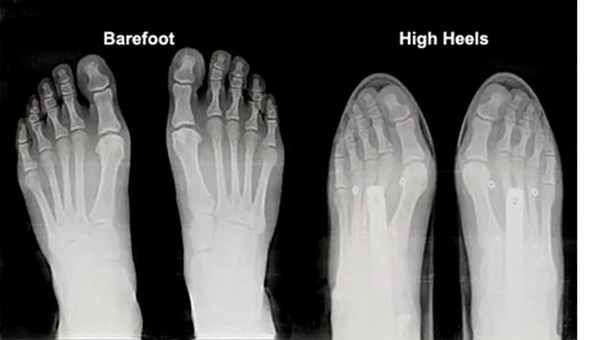

Рис. 1. Рентгенограмма стоп: слева - без обуви, справа – в узкой обуви на высоких каблуках. Компрессия и девиация пальцев стопы, вальгусная деформация большого пальца